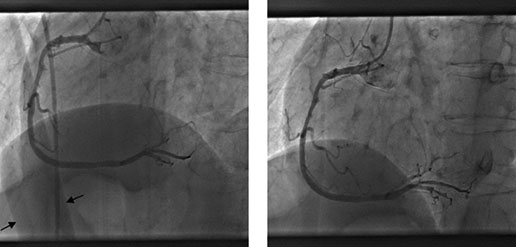

Streszczenie Wprowadzenie i cel: W ochronie radiologicznej standard pacjenta referencyjnego stanowi kryterium odniesienia względem dawek promieniowania, jakich nie należy przekraczać w diagnostyce i leczeniu z użyciem promieniowania jonizującego. Celem badania była analiza porównawcza pomiędzy wartościami opisującymi wzrost i masę ciała pacjentów, którym wykonano angioplastykę wieńcową a standardem pacjenta referencyjnego płci żeńskiej i męskiej. Materiał i metoda: Grupę badaną stanowiło 372 pacjentów, którym wykonano zabieg…